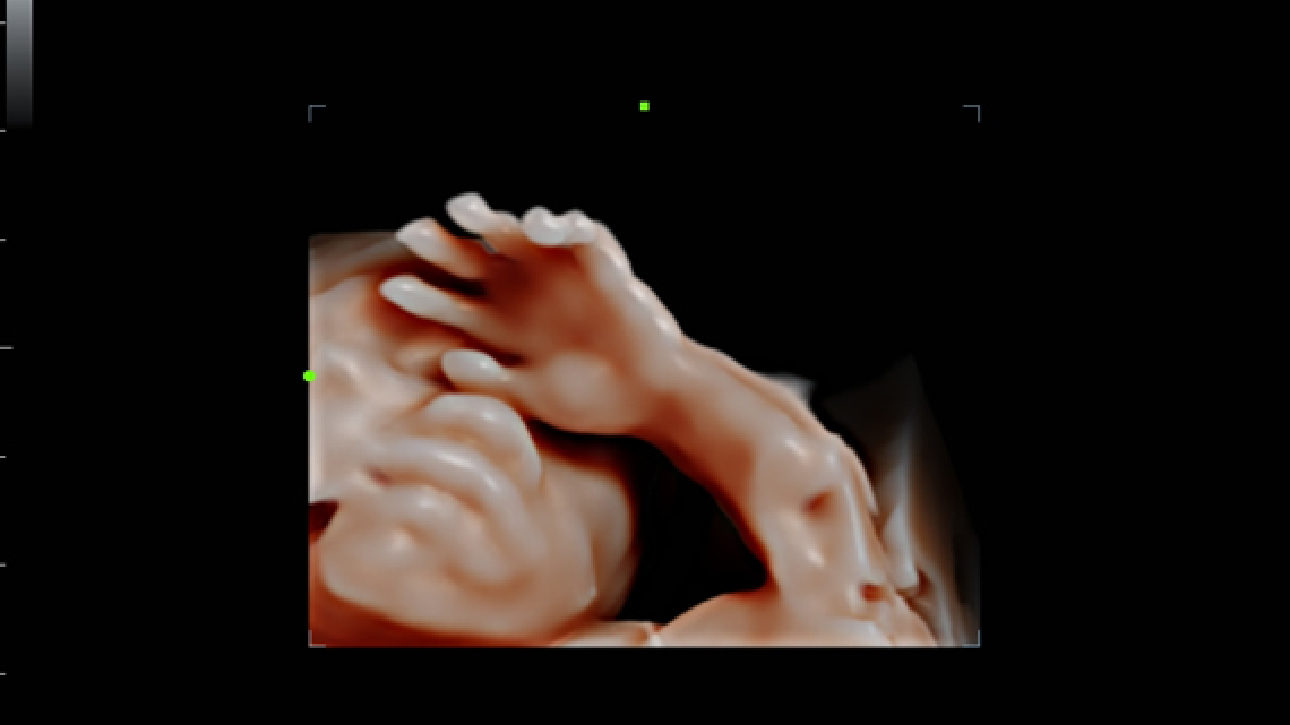

Imagens clĂnicas